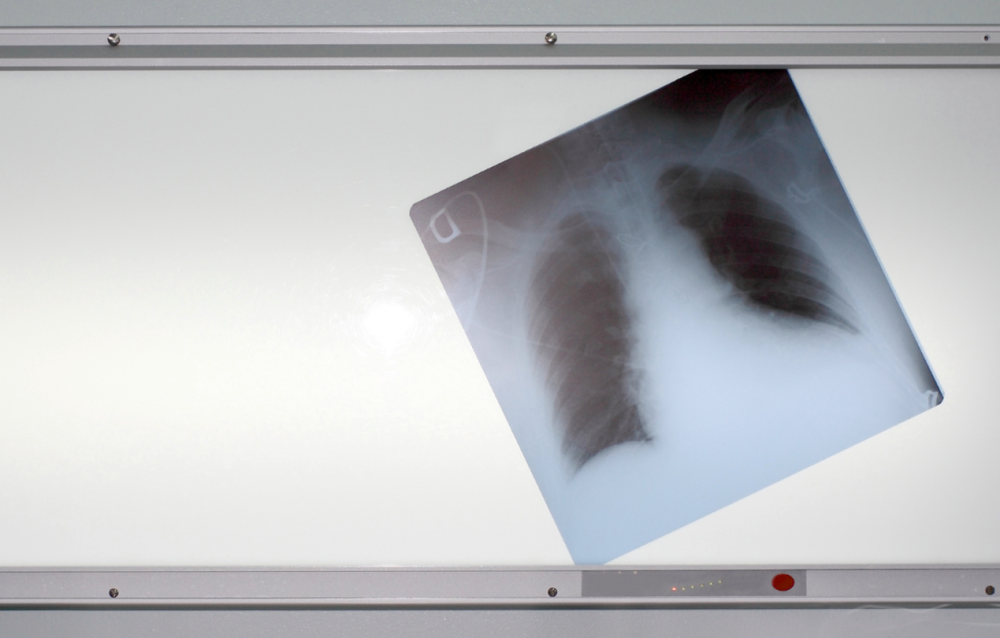

Курение оказывает системное влияние. Табачный дым содержит десятки канцерогенных соединений, которые разносятся с током крови по всему организму. Эти вещества проникают в ткани, нарушая клеточные процессы. Страдают не только легкие, но и органы, не связанные с дыханием на первый взгляд.

Как курение влияет на организм человека?

Каждый человек хотя бы раз в жизни слышал, что курение вредно для здоровья и является фактором риска развития разных видов онкологических заболеваний. Но как именно курение оказывает негативное воздействие?

Курение признано основным фактором риска заболеваний легких, сердца и нервной системы.